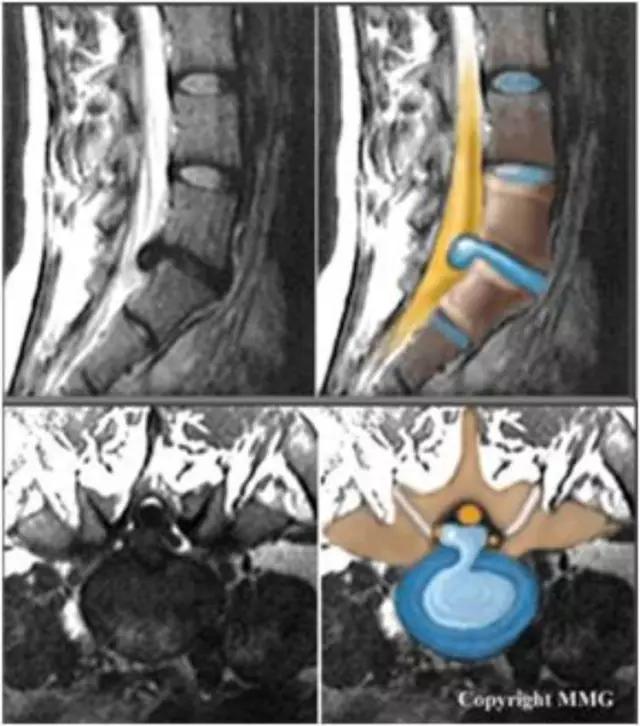

半月板损伤的分度——

Normal:正常的半月板为均匀的低信号。Grade1:半月板内部小灶性的类圆形信号增高影,未达半月 板表面,代表退变性改变。Grade2:半月板内部线形的中等信号增高影,未达半月板表面,代表退变性改变。Grade3:达到半月板关节面的异常信号,可为线形或不规则形,通常代表半月板撕裂。韧带损伤的分级(对所有韧带适用)——Grade1:韧带内损伤,无长度改变。Grade2:韧带内损伤并长度延长。Grade3:完全性韧带撕裂。